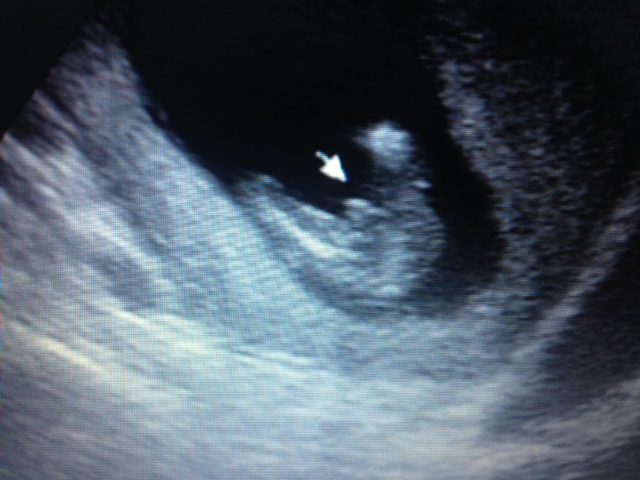

These pictures were from my 14week 1 day ultrasound. Boy or girl?! Help me out :crawl:

Early but looks boy to me. Girls at 14 weeks, if they still have anything between the legs, is usually short and very pointy. I think this is a boy.

I'd say it's very very boyish. It's still a little early, but at this point I don't think you'd see such clear boy parts if the baby were actually a girl. My potty shot from 13 weeks was very clearly girly.

Thank you ladies! I also think boy. I've just never had an ultrasound done this early, so the boy "parts" look completely different that what I am used to seeing! My 20wk anatomy ultrasound is next week- I will be sure to let everyone know what gender is confirmed :crawl: